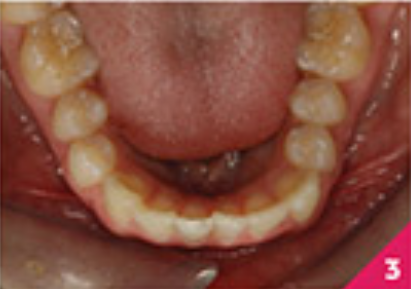

В пацієнтки не було жодних проблем зі здоров'ям та стоматологічних захворювань, крім, мінімальної гіпертрофії ясен на центральних різцях нижньої щелепи. Дотримання гігієни ротової порожнини було відмінним. У пацієнтки був скелетний I клас зі співвідношенням на молярах по I класу.

Праве ікло верхньої щелепи було в перехресному перекритті, а різці верхньої і нижньої щелепи були нахилені. Скупчення зубів було помірним у верхньому зубному ряді та легким у нижньому.

На фото зображено розташування зубів перед початком лікування.